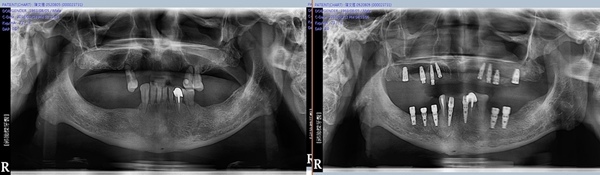

↑植牙前後